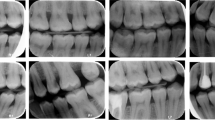

Pulpal calcifications are discrete hard calcified masses of varying sizes in the dental pulp cavity. This study is aimed at measuring the performance of the YOLOv4 deep learning algorithm to automatically determine whether there is calcification in the pulp chambers in bite-wing radiographs.

In this study, 2000 bite-wing radiographs were collected from the faculty database. The oral radiologists labeled the pulp chambers on the radiographs as “Present” and “Absent” according to whether there was calcification. The data were randomly divided into 80% training, 10% validation, and 10% testing. The weight file for pulpal calcification was obtained by training the YOLOv4 algorithm with the transfer learning method. Using the weights obtained, pulp chambers and calcifications were automatically detected on the test radiographs that the algorithm had never seen. Two oral radiologists evaluated the test results, and performance criteria were calculated.

The results obtained on the test data were evaluated in two stages: detection of pulp chambers and detection of pulpal calcification. The detection performance of pulp chambers was as follows: recall 86.98%, precision 98.94%, F1-score 91.60%, and accuracy 86.18%. Pulpal calcification “Absent” and “Present” detection performance was as follows: recall 86.39%, precision 85.23%, specificity 97.94%, F1-score 85.49%, and accuracy 96.54%.

The YOLOv4 algorithm trained with bite-wing radiographs detected pulp chambers and calcification with high success rates.